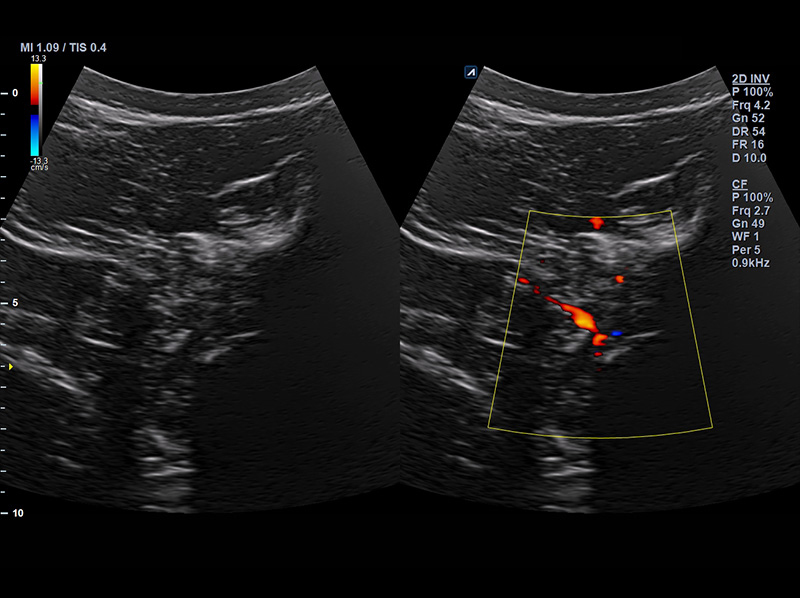

SC2-11H

X+ Crystal Signature™ Microconvex(2~11MHz)

Application:

Abdomen, Pediatric, OB/GYN, Urology, EM